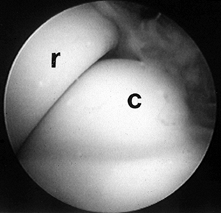

into the joint under direct visualization. With the arthroscope in the

anteromedial portal, it is easy to visualize the radial head and

capitellum (Fig. 82.12).

Pronation and supination of the forearm provides additional

visualization of the radial head. The coronoid process can also be seen

if the scope is carefully withdrawn from the joint. The ulnar-radial

articulation can be inspected through this portal. Small loose bodies

are often found in this location. The anteromedial portal is critical

for viewing the radial head, as visualization of the radial head from

the anterolateral portal is very poor.

Figure 82.12. Arthroscopic view of the radial head (r) and the capitellum (c) from the anteromedial portal. -